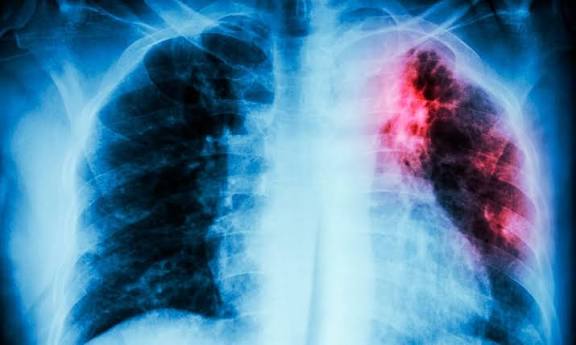

El estado registra el primer lugar nacional en casos de Tuberculosis respiratoria, con 1,792 casos acumulados en 2025. Además, presenta la incidencia más alta del país en infecciones parasitarias, liderando los reportes de Ascariasis, con 3,187 casos.